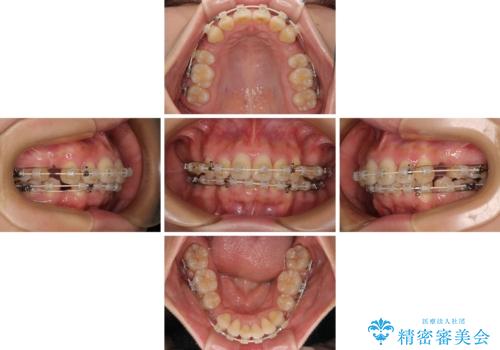

- 矯正装置

- 審美装置

想像以上に咬合力が強く、抜歯したスペースを閉じきるまでに長期間を要することとなりました。